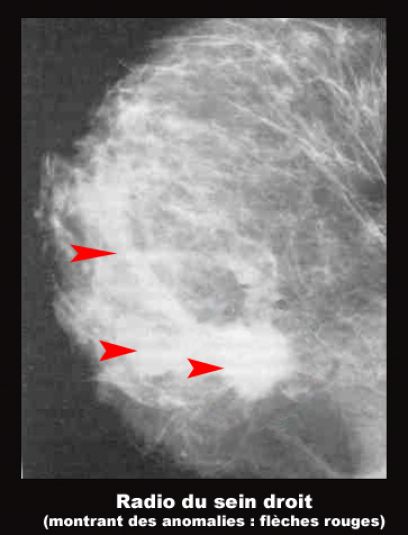

La mammographie est une radiographie des seins qui permet d'obtenir des images de l'intérieur du sein à l'aide de rayon x et de diagnostiquer d'éventuelles cancers ou anomalies.

Une mammographie peut-être réalisée soit dans le cadre d'un dépistage du cancer du sein, soit en présence de symptômes.